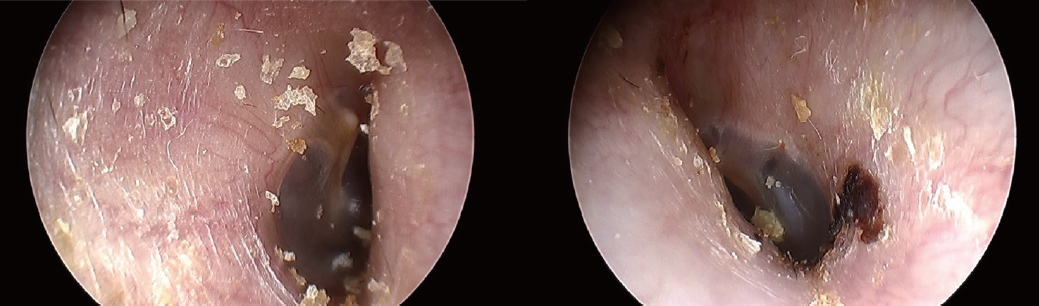

증 례48세 남자가 1주일 전부터 시작된 양측 청력저하로 내원하였다. 회전성 어지러움이 동반되었으며 과거력 및 가족력에서 특이사항은 없었다. 신체진찰상 양측 외이도 및 고막 모두 정상 소견이었으며(Fig. 1), 그 외 이비인후과적 검사에서 특이사항은 없었다. 순음청력역치를 6분법[(500 Hz+1000 Hz×2+2000 Hz×2+4000 Hz)/6]으로 계산했을 때 우측 기도 청력 120 dB, 골도 청력 66 dB, 좌측 기도 청력 51 dB, 골도 청력 34 dB로 우측 고심도 난청(profound hearing loss), 좌측 중등도 난청(moderate hearing loss)이 확인되었다. 양측 돌발성 난청 의증하에 7일 동안 매일 정맥 내 dexamethasone 10 mg 및 양측 고막 내 스테로이드 주입술(우측 6회, 좌측 5회)을 시행하면서 지속적으로 청력검사를 시행했으며 입원 2일째 청성뇌간 유발반응 검사(auditory brainstem response exam)에서 양측 전농을 확인했다(Fig. 2).